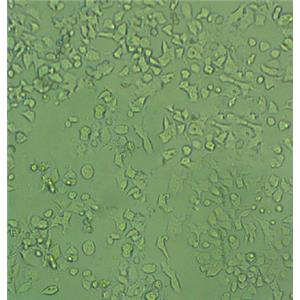

"MNNG/HOS Cells人骨肉瘤细胞系(提供STR图谱)

" "传代比例:1:2-1:4(首次传代建议1:2)

" "背景信息:骨肉瘤;女性

" "换液周期:每周2-3次

" "生长特性:贴壁

" "MNNG/HOS Cells人骨肉瘤细胞系(提供STR图谱)

" "形态特性:详见细胞说明书

" "MNNG/HOS Cells人骨肉瘤细胞系(提供STR图谱)

" "MNNG/HOS Cells人骨肉瘤细胞系